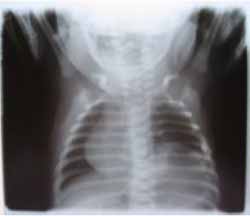

Ingresó a la Unidad de Cuidados Intensivos Neonatales (UCIN) por prematurez, con una evolución caracterizada por polipnea en las primeras horas, cianosis perioral y signos de distress respiratorio. Se obtuvo una placa radiográfica de tórax que demostró dextrocardia con integridad del resto de las estructuras torácicas. La auscultación cardíaca no reveló presencia de soplos ni arritmias.

El ejemplo de nuestro caso reporte es claro, cuando se observaron alteraciones respiratorias que motivaron el empleo de una radiografía torácica y se encontró la dextrocardia como hallazgo radiológico. [Figura 2]

Figura 2. Placa radiográfica